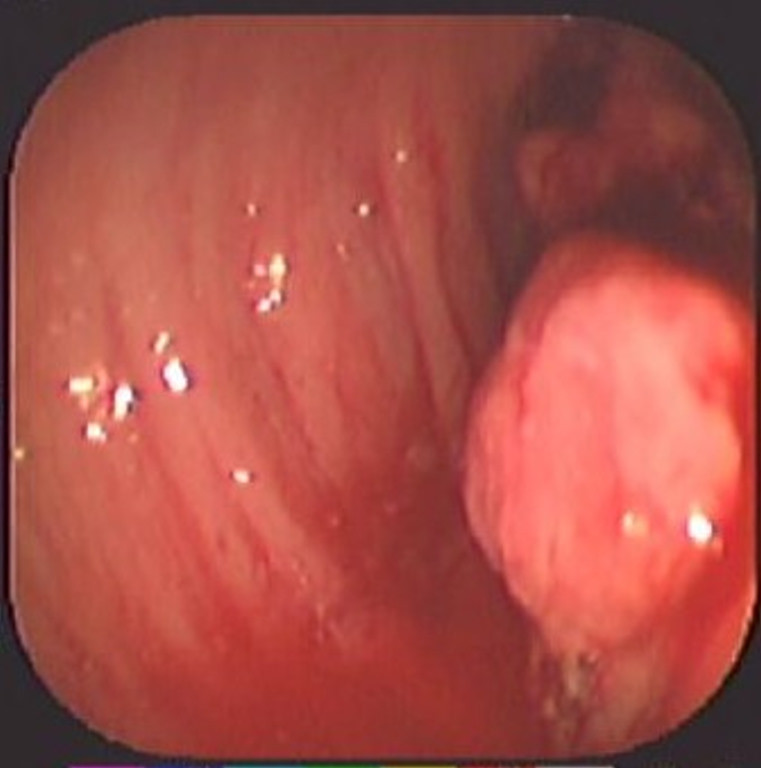

Cáncer de Colon

Envíado por Dr. Carlos Ernesto Arévalo